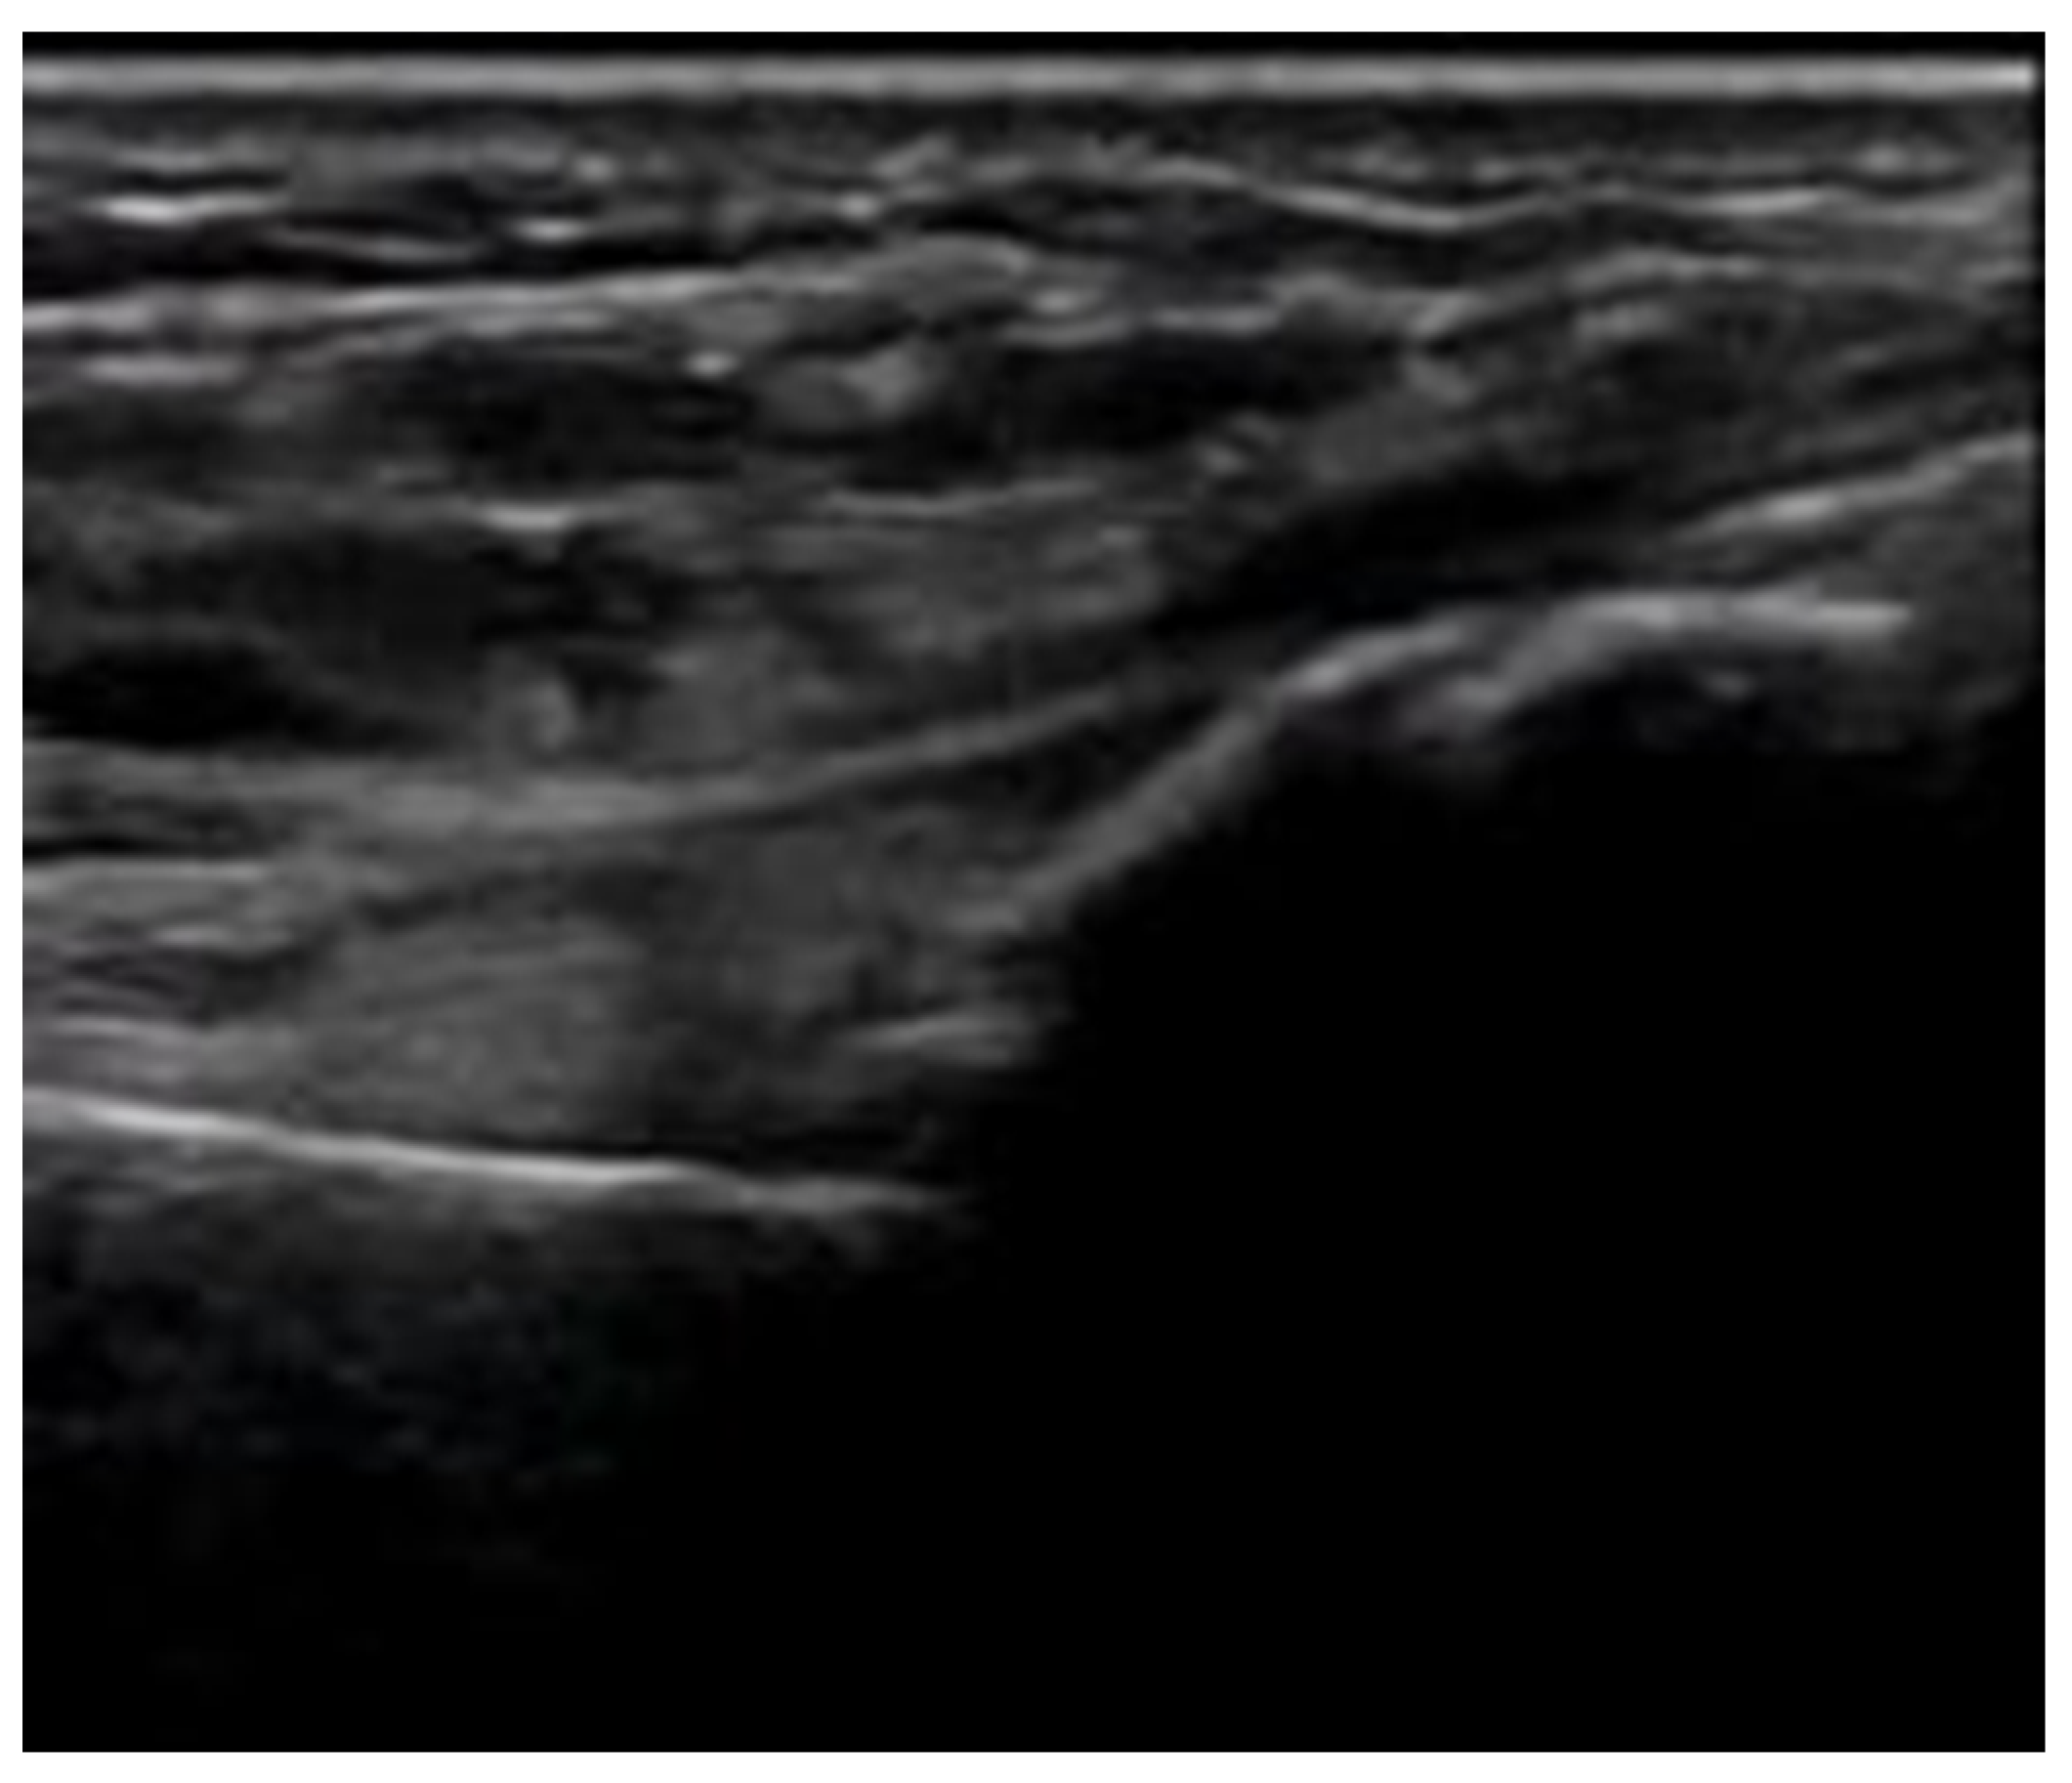

4.2. Sonoanatomy of Fractures [Figure 5, Figure 6, Figure 7 and Figure 8]

- Irregularity, interruption, or gaps in the cortical line: the cortical bone normally appears as a continuous, bright echogenic line, which is interrupted or irregular in the presence of a fracture.

- Bulging or abnormal angulation of the cortical layer: deformities or outpouchings of the normally straight cortical surface indicate displacement or bending at the fracture site.

- Dislocation: misalignment of bone fragments, visible as separation or shift from their normal anatomical position.

- Angulation: an abnormal angle formed between fracture fragments, indicating malalignment.